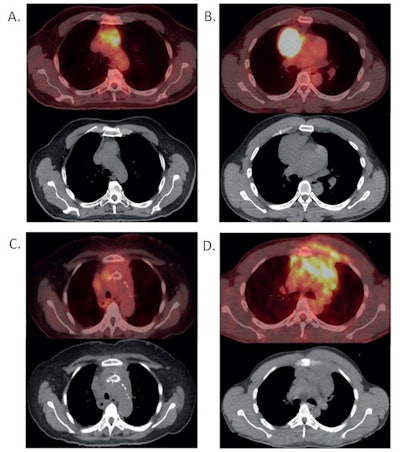

Panel A and B demonstrate resectable disease. Panel C and D demonstrate unresectable disease that would benefit from systemic therapy. Panel A demonstrates a thymoma that appears suitable for resection on PET/CT imaging (above) and CT imaging (below). Panel B demonstrates a resectable lymphoma on PET/CT imaging (above) and CT imaging (below). Panel C demonstrates an unresectable thymoma on PET/CT imaging (above) and CT imaging (below). This thymoma is unresectable given invasion of the mass into the great vessels. Stents were placed prior to imaging to relieve compression by the mass. Panel D demonstrates an unresectable lymphoma on PET/CT imaging (above) and CT imaging (below). This lymphoma is unresectable given the direct extension of the tumor into the ribs and surrounding muscle. Image courtesy of the Journal of Thoracic and Cardiovascular Surgery.The median SUVmax of thymoma and lymphoma differed dramatically, according to the findings: 4.35 for thymomas versus 18 for lymphomas (p < 0.001). An SUVmax < 12.85 was associated with thymoma with 100% sensitivity and approximately 89% positive predictive value, while SUVmax < 7.5 demonstrated 100% positive predictive value for thymoma.

In other words, tumors with SUVmax < 7.5 are likely thymoma and thus can be surgically removed without biopsy, while tumors with SUVmax > 7.5 should be biopsied to rule out lymphoma, the researchers suggested. Lymphoma is likely with SUVmax > 12.85, they added.